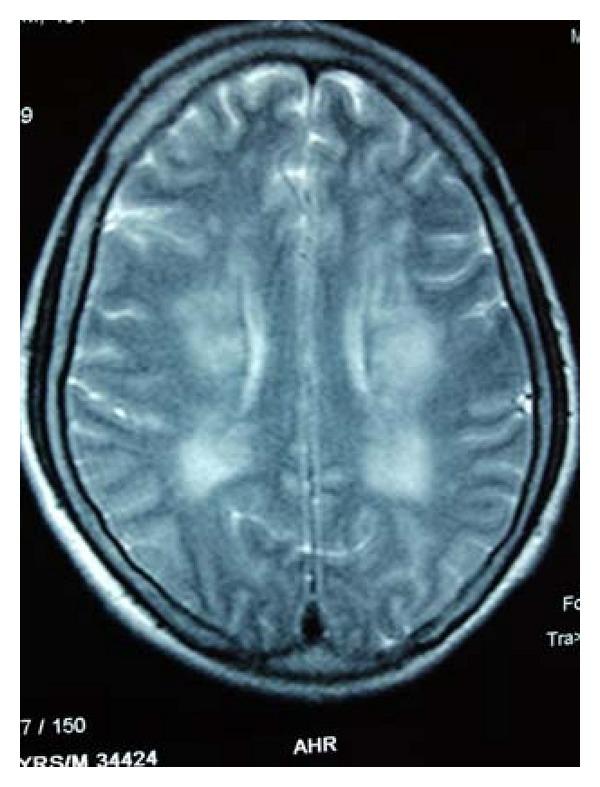

Cirrhotic or hepatic myelopathy is a rare neurological complication of chronic liver disease usually seen in adults and presents as a progressive pure motor spastic paraparesis which is usually associated with overt liver failure and a surgical or spontaneous systemic portocaval shunt. We describe the development of progressive spastic paraparesis, in a patient with alcoholic cirrhosis with portal hypertension and portal colopathy who presented with the first episode of hepatic encephalopathy. The patient had not undergone any shunt procedure.